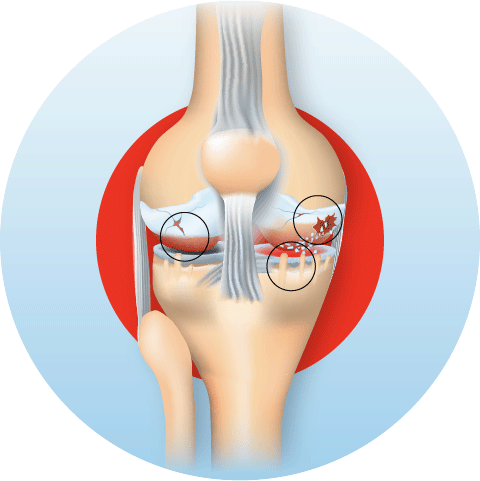

As the hyaline cartilage thins and erodes, bone rubs on bone, triggering pain, swelling, and the formation of bony spurs (osteophytes). The synovium becomes inflamed, producing excess joint fluid the familiar swollen, warm knee of a flare-up. Over time, the joint space narrows, and the leg may bow inward (varus) or outward (valgus) as the joint deforms.

Definite osteophytes; slightly reduced joint space. Ideal window for regenerative therapies — PRP, hyaluronic acid, BMAC.

Significant cartilage loss; multiple osteophytes. Combination of BMAC, genicular nerve RFA, and bracing delivers best results.

Near-complete cartilage loss. Surgery may be considered, but for unsuitable patients, genicular RFA + BMAC remains highly effective for pain control.